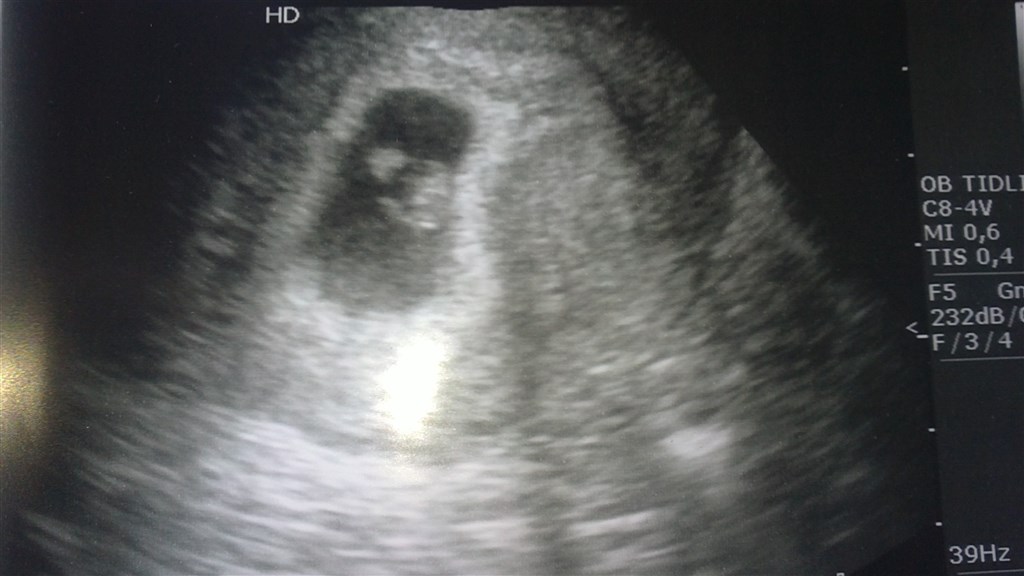

og vi så et hjerte der bare slog der ud af

jeg er så lettet

jeg blev rygget en dag frem så jeg er 6+6 idag